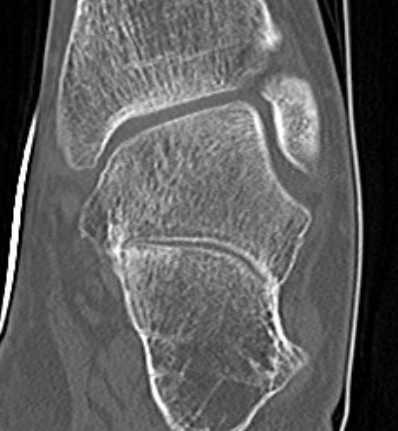

CT

TC coalition middle facet

Complete synostosis of the medial TC joint with OA of the posterior subtalar joint